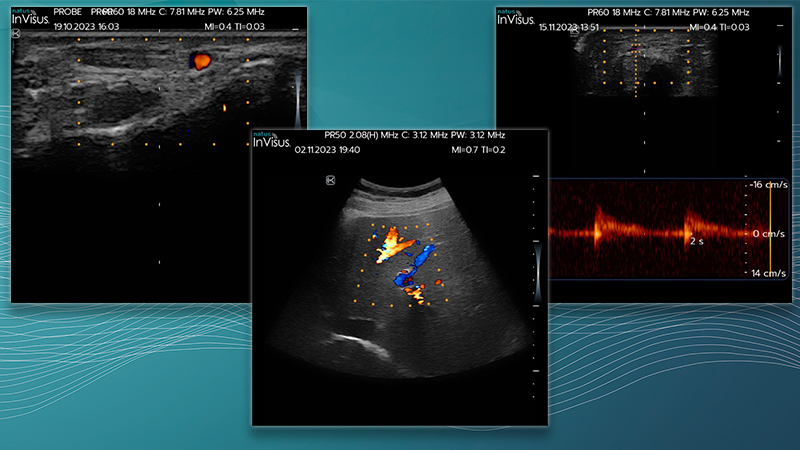

Il nuovo ecografo neuromuscolare InVisus Pro è progettato per consentire al team di identificare facilmente le strutture e punti di riferimento, aumentando la produttività e l’accuratezza, con uno schermo LED da 7″ che visualizza immagini full HD. Ottimizzato per le differenze di contrasto e struttura, InVisus Pro offre al personale medico un chiaro vantaggio in termini di sicurezza diagnostica.

L’ecografo neuromuscolare InVisus Pro è un tablet compatto che consente di visualizzare informazioni clinicamente utili per supportare il sistema EMG, direttamente nel punto di interesse. Visualizza i nervi e i muscoli, identifica rapidamente le neuropatie e le miopatie, o addirittura guida il posizionamento degli aghi.

Immagini HD di alta qualità

L’alta risoluzione visualizzata su uno schermo LED da 7″ consente al team di identificare facilmente strutture e punti di riferimento, aumentando la produttività e la precisione.

Come passo verso il futuro dell’ecografia neuromuscolare integrata di Natus, InVisus Pro è stato progettato per integrare qualsiasi sistema EMG, compresi i sistemi Nicolet EDX, UltraPro, Keypoint G4 e Keypoint Focus. Questa soluzione compatta e portatile è stata progettata appositamente per fornire un supporto in tempo reale al personale medico, proprio nel punto di assistenza. InVisus Pro offre anche la flessibilità di regolare facilmente le impostazioni e produrre immagini complete di misurazioni e annotazioni da aggiungere ai referti EMG.

Misurazioni